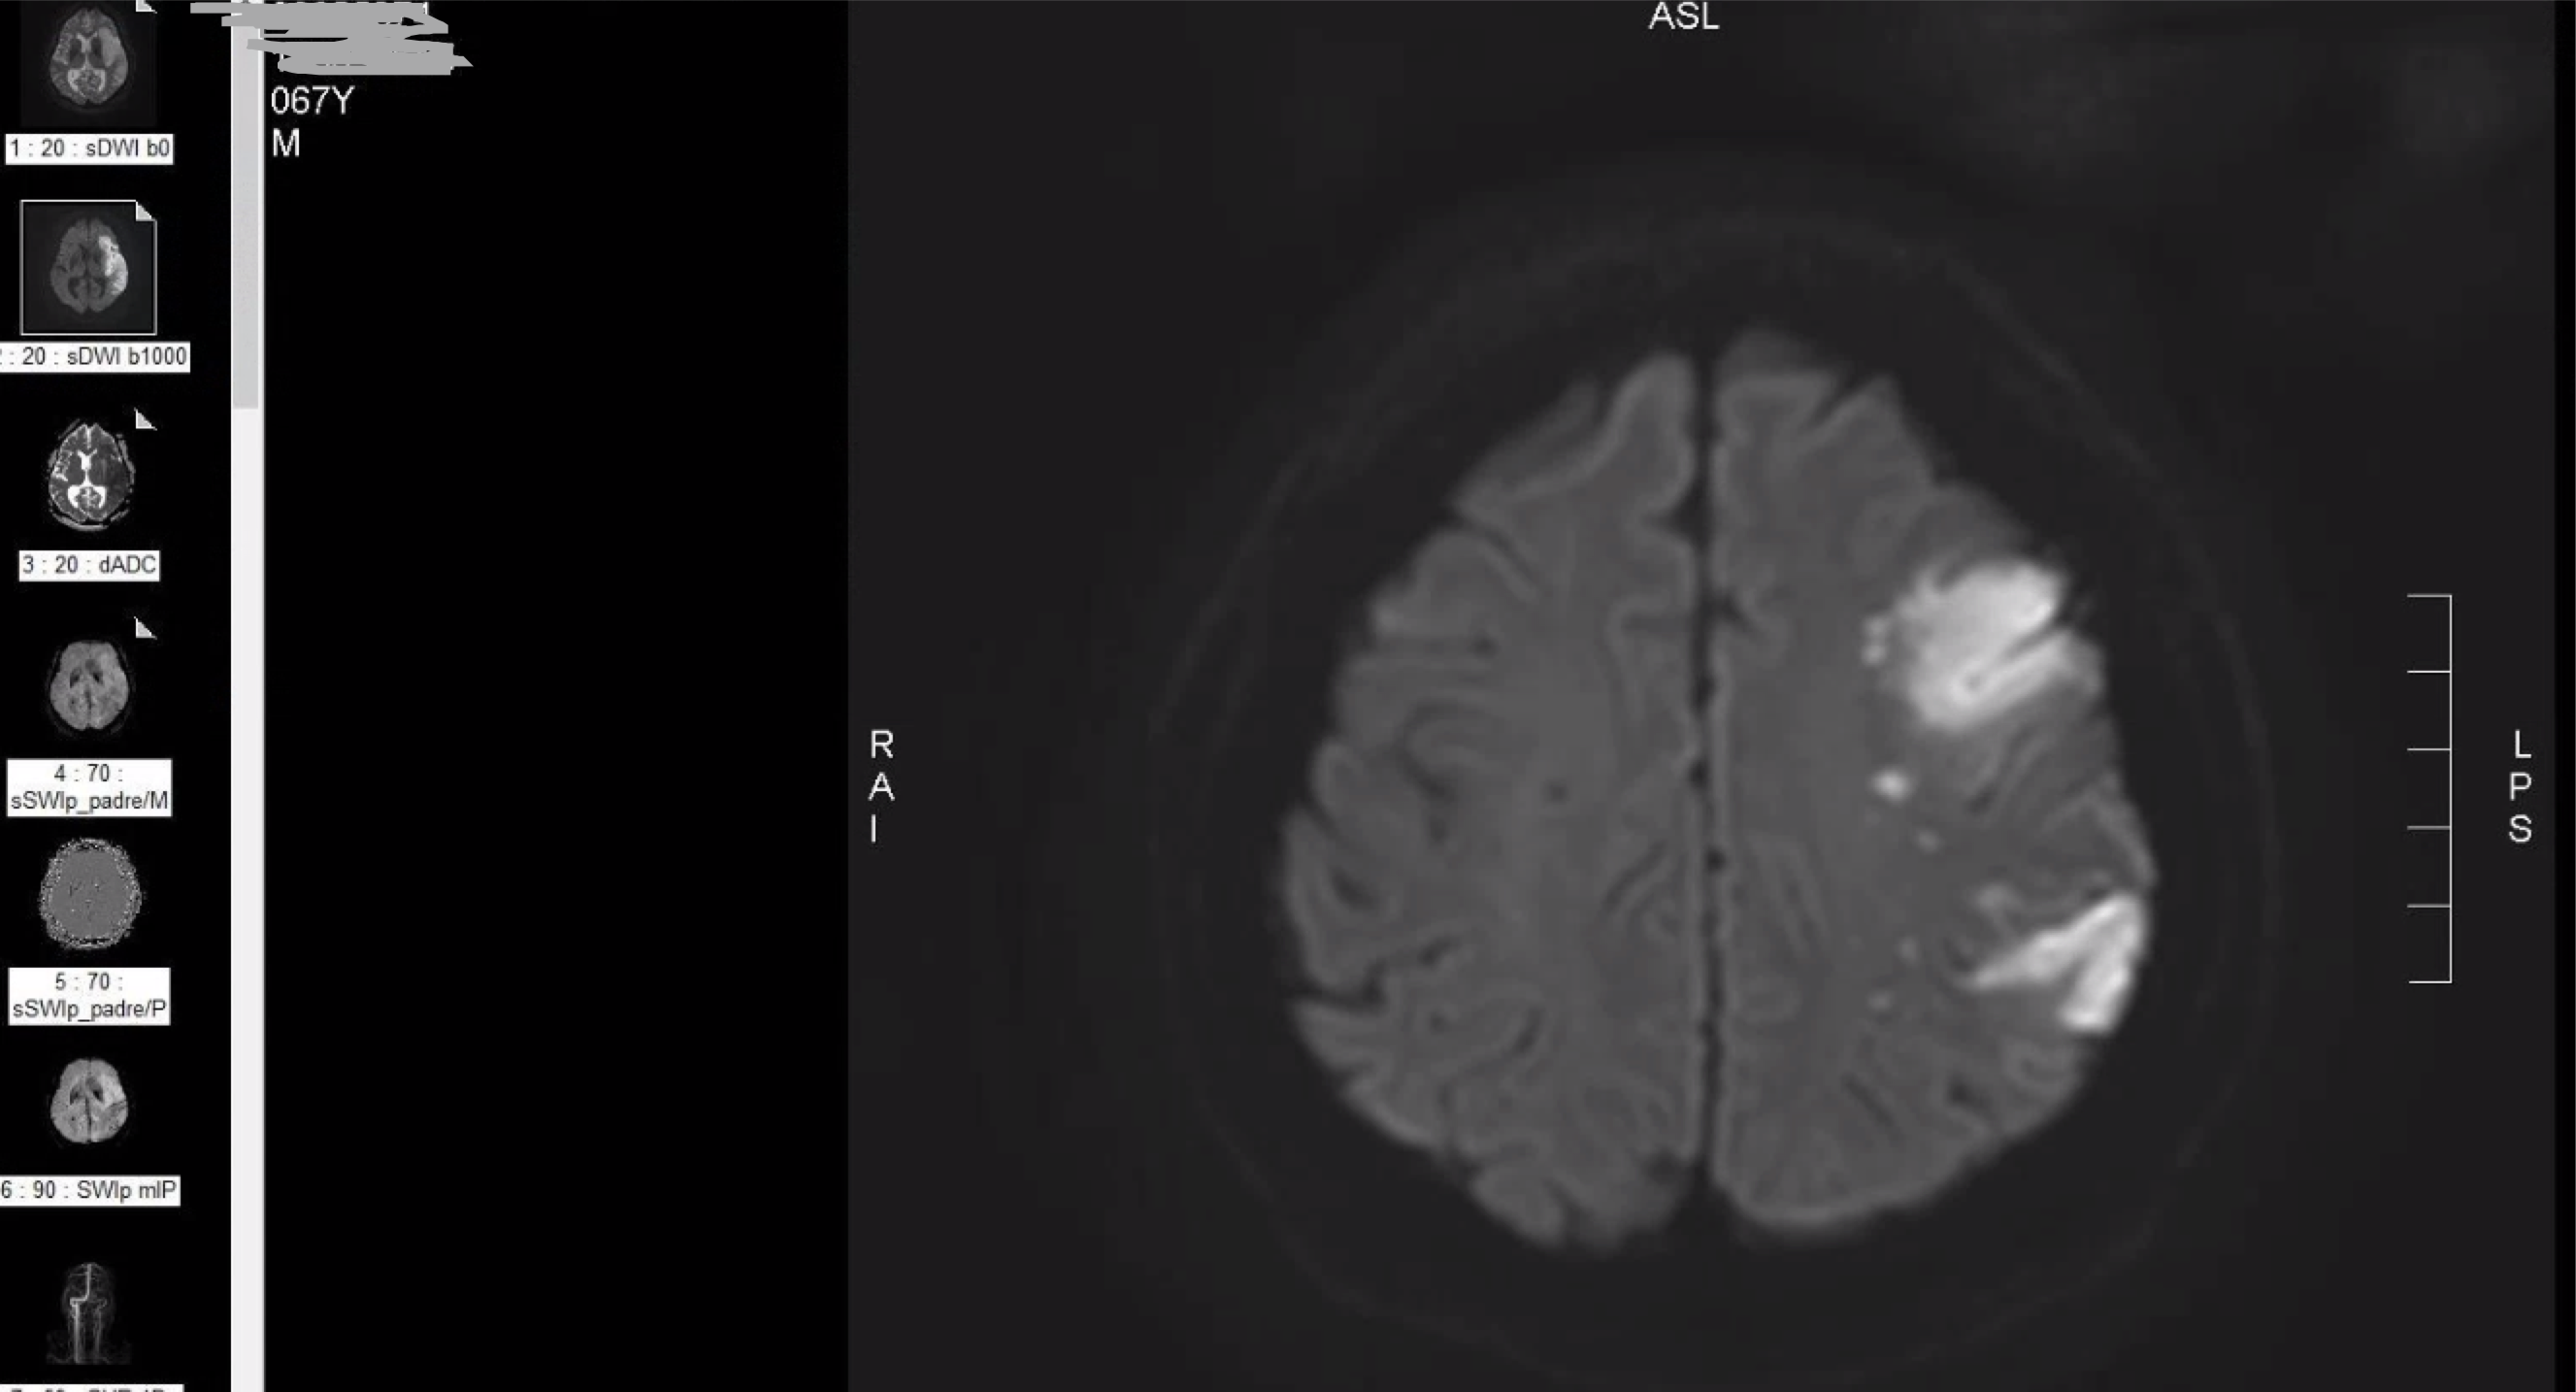

M/68

right hemiplegia d/t cbr. infarction 2020.10.5.

left MCA territory infarction

severe cognitive impairment

global apahsia

STEMI 2019.8.29. stent x2

a. fib